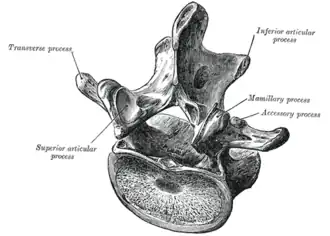

Kenmerkend voor lendenwervels is dat zij, in vergelijking met de andere wervels, het grootste wervellichaam (lat.: corpus vertebrae) hebben. Tevens is het doornuitsteeksel (lat.: processus spinosus) erg groot in vergelijking met de andere wervels, en wijst het recht naar achteren. De gewrichtsuitsteeksels (lat.: processus articularis) hebben een oriëntatie in het zijwaartse vlak, waardoor er in dit deel van de wervelkolom voornamelijk voor/achterwaartse bewegingen plaats kunnen vinden.